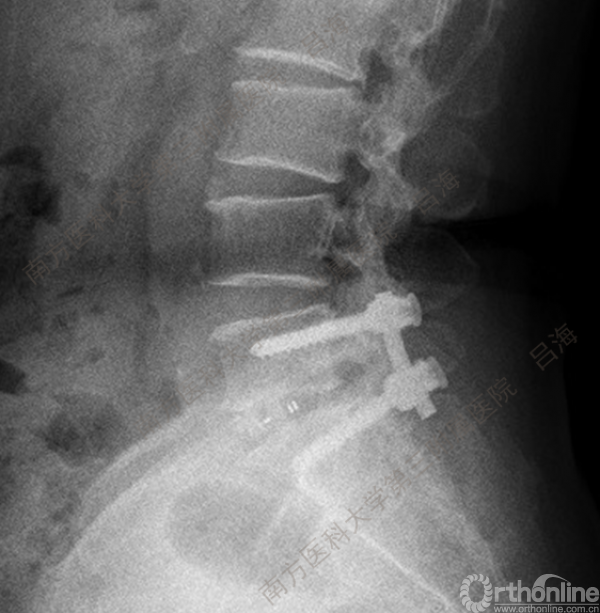

随着社会老龄化进程加快,胸腰椎退行性病变的治疗已经成为脊柱学术界的一个热点话题。MIS-TLIF手术可以治疗多种不同的胸腰椎退行性疾病,南方医科大学第三附属医院吕海教授结合病例为我们一一展示了该术式在治疗不同胸腰椎疾病时的具体手术过程。